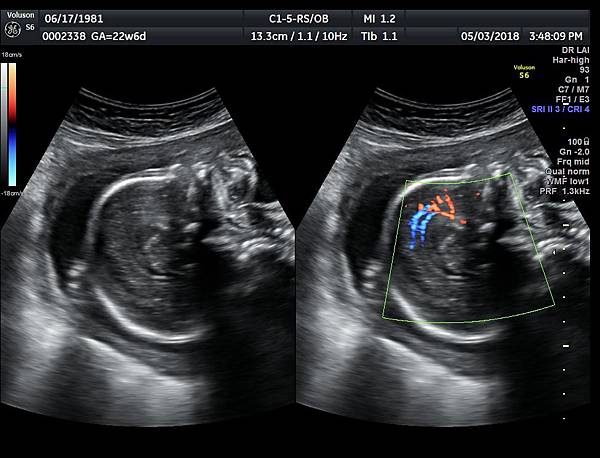

2016年8月4日在執行胎兒高層次超音波檢查時,我發現胎兒腦部的CSP(cavum septum pellucidum)很不清楚(附圖1~4),遇到這種情況,需要仔細評估胎兒腦部的駢胝體,因為CSP的天花板是駢胝體,CSP不明顯時,要合理的懷疑駢胝體沒有發育,或駢胝體下方有長東西(例如lipoma),駢胝體是連接左右大腦的神經纖維所組成。

檢查胎兒駢胝體是有技巧的,需要兩個切面:

1. 矢狀切面(sagittal plane):駢胝體呈現類似三明治的中間黑色部分,上面一層薄薄白色的區域是callosum sulcus,打上flow可以看到pericallosum artery在駢胝體上面的周圍,pericallosum artery來源是前腦動脈,參考附圖 6~10,三明治下面白白的部分是和CSP做比較得到的,如果這一層長lipoma(附圖 5),CSP很可能看不到。